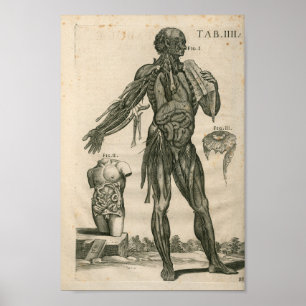

1741 Spieranatomie Afdrukken Poster

Prijs€ 18,70